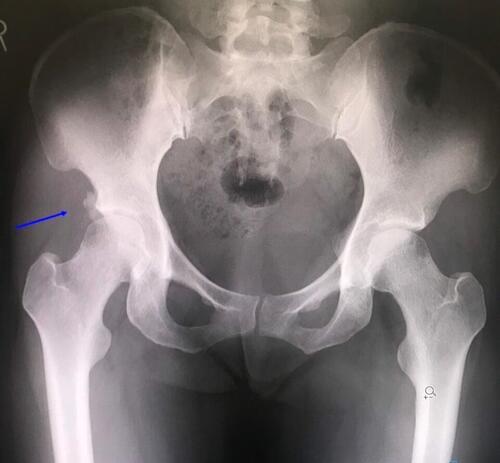

ここ数日の「まる接骨院」流行病。 空手選手の股関節周囲の痛みでございます。 どん...

ここ数日、鼡径部周辺の痛みの症状で ご来院される患者さんが急増中 サッカーなどの...